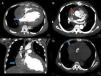

We present a case of a 37-year-old hypertensive male admitted with dyspnea on exertion, orthopnea, paroxysmal nocturnal dyspnea, fatigue and bilateral leg edema. The echocardiogram revealed a dilated left ventricle (diastolic diameter 79 mm, systolic diameter 70 mm) with severely depressed left ventricular function (20% by Simpson's method) and severe aortic regurgitation. He underwent aortic valve replacement and reduction of the ascending aorta. The patient's clinical condition improved significantly but discharge was delayed due to social problems. Three weeks after surgery he suddenly became hypotensive, tachycardic, sweating, pale with cool extremities, and anuric. The electrocardiogram showed sinus tachycardia with left ventricular hypertrophy, and the bedside echocardiogram revealed a medium-sized echogenic mass measuring 9cm×6cm, causing almost complete collapse of the right atrium, and mild (6 mm) circumferential pericardial effusion (Figure 1A–D). Prosthetic function was normal. The emergency computed tomography (CT) scan showed a hematoma measuring 9.4cm×8.5cm×5.9cm compressing the right atrium and an active bleeding point 2.4 cm above the aortic prosthesis in the ascending aorta (Figure 2A and B). The patient was transferred to the cardiothoracic surgery center. Surgical exploration revealed a large organized pericardial hematoma compressing the right atrium. It was removed and the aortic suture was reinforced. The recovery was uneventful. One month later he was clinically well and the echocardiogram showed no pericardial effusion, a functional biological valve and severely depressed left ventricular function.